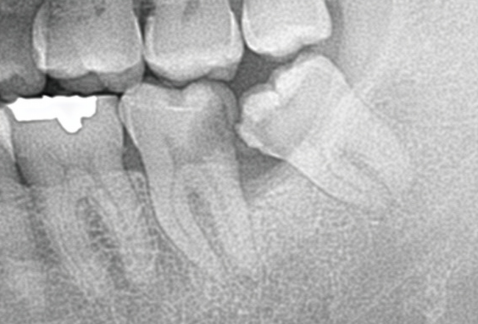

8.手前の歯の根を押す場合、押された歯の根は溶けてしまいます

一番左の親知らずが、大事な隣の歯の根を溶かしてしまいました。

下の親知らずが、前の歯の根を溶かしてしまいました。

9.親知らずの歯磨きが不十分で歯槽膿漏になったら骨が溶け、手前の歯の根の周りの骨も溶けます

一番右の親知らずが、大事な隣の歯の根を溶かしてしまいました。